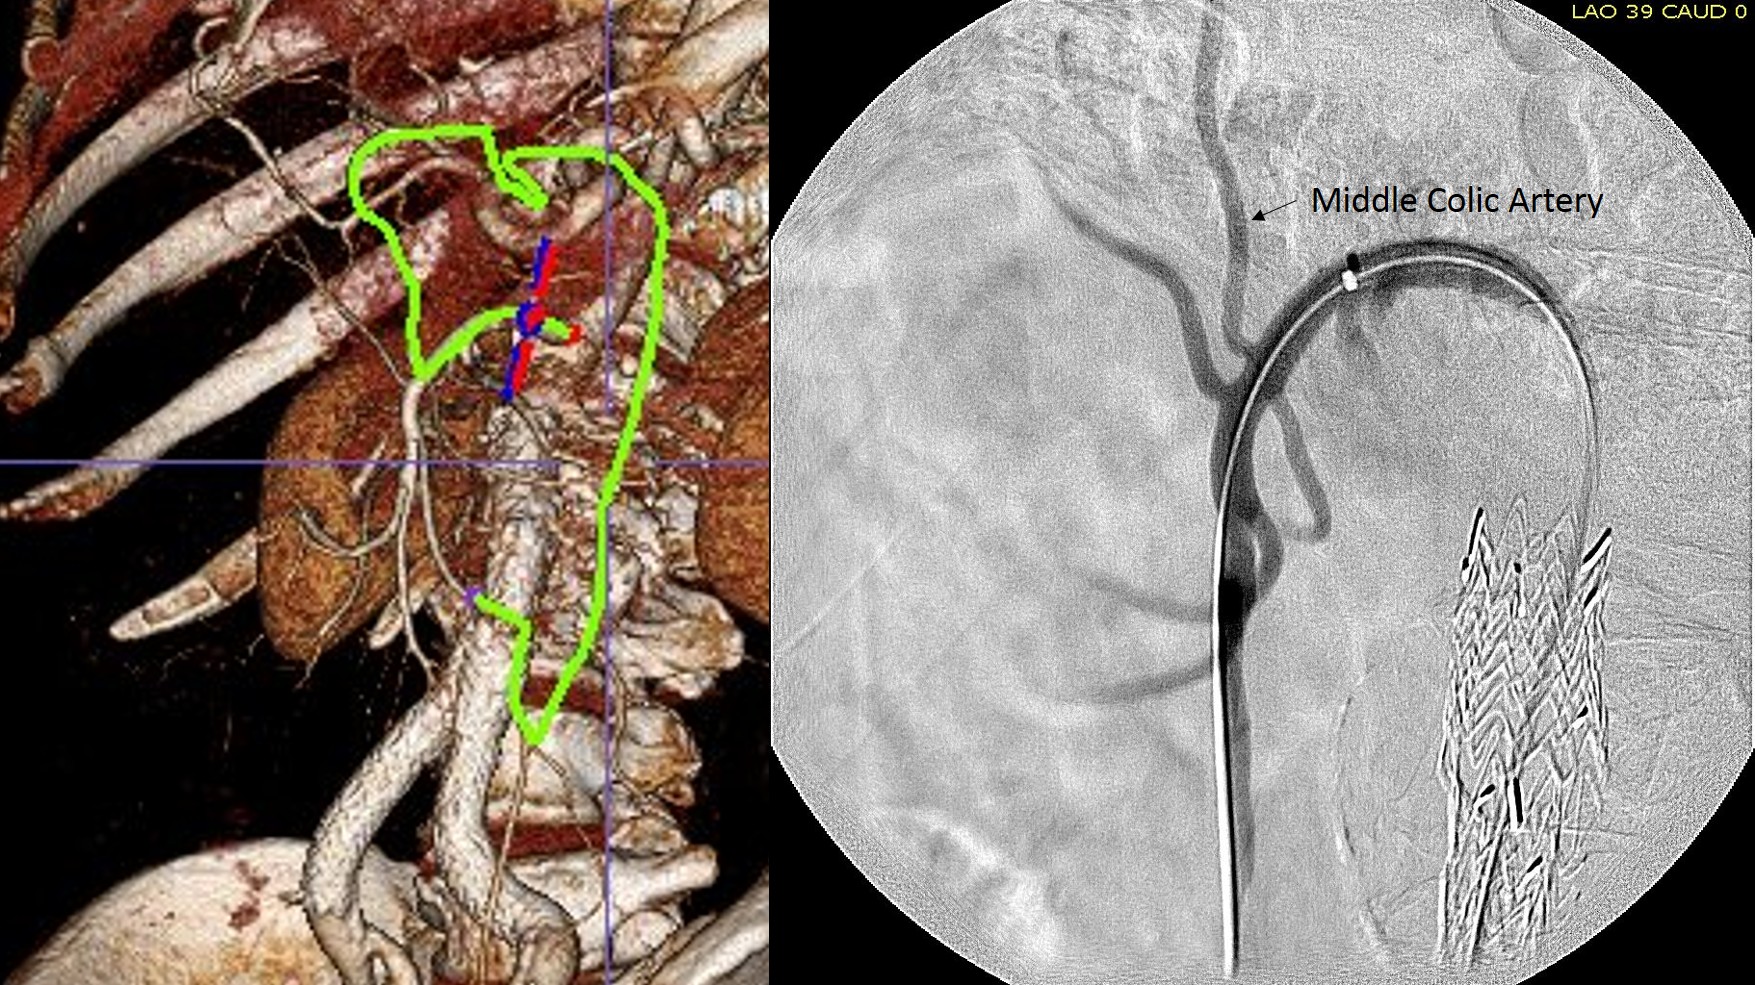

The centerline from the SMA into the middle colic artery shows a meandering but patent path via the Arc of Riolan to the left colic artery to the inferior mesenteric artery. In my experience this is straightforward to access selectively from the femoral approach, but it illustrates for the trainees the concept of building up access which I refer to as building the intervention machine.

The first step in the access involves getting stable footing in the SMA. Selective access can be performed with a shaped catheter, and once accessed, a Rosen wire is used to track in a curved long sheath. Parking this sheath in the proximal SMA forms the foundation of this machine. The next step is access into the middle colic artery.

The CTA is particularly helpful in identifying the middle colic on the 3DVR projection. Selection of this is straightforward with a an angle catheter which I place a Tuohy Borst connector. This is the second stage of the machine, because further access with 0.35guage wires and catheters could result in spasm. This second sheath access (the Tuohy turns the catheter into a sheath) of the middle colic allows for selective 0.18 gauge catheters and wires to make the final step to the IMA and the AAA.

The access machine concept is important for planning interventions. Every major branch or turn needs to be crossed by your ultimate access sheath, if you want to avoid having to arduously reaccess those points, and building up a telescoping layer of sheaths is very handy. Every interventional case is done at some distance away from the access point on the skin, and so some though has to be given to how you will build that machine.